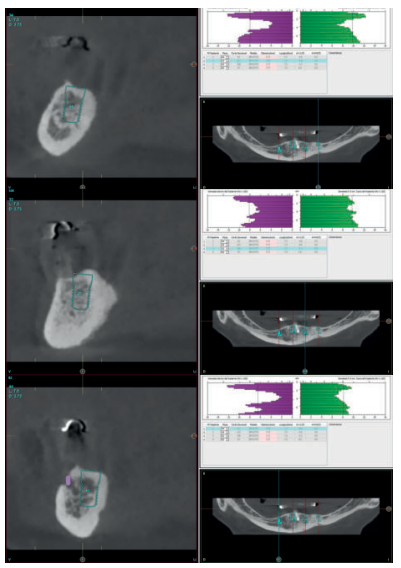

Se realiza un CBCT dental para la planificación del caso y poder rehabilitar el maxilar superior e inferior. En la mandíbula se planifica retirar los dos implantes de forma atraumática (mediante el kit de extracción a contra-torque) y la inserción de cuatro implantes para la confección de una nueva prótesis implanto-soportada. Los cortes de planificación muestran la necesidad de que los implantes insertados sean cortos y algunos de ellos, como el caso del implante en posición 44, por lingual del nervio dentario. (Figuras 5-7).

En el caso del maxilar superior, la atrofia es combinada, existiendo una gran atrofia vertical en los sectores posteriores que requiere la inserción de implantes cortos y extra-cortos, para evitar una elevación de seno a ese nivel. En las zonas anteriores (de premolar a premolar) existe una extrema reabsorción horizontal que obliga a la inserción de implantes estrechos, siendo los seleccionados cuatro implantes de plataforma reducida (3.0) y un implante de plataforma reducida Core en una zona de transición entre la atrofia anterior y posterior, que presenta una atrofia mixta (zona de 15-16) (Figuras 8-10).